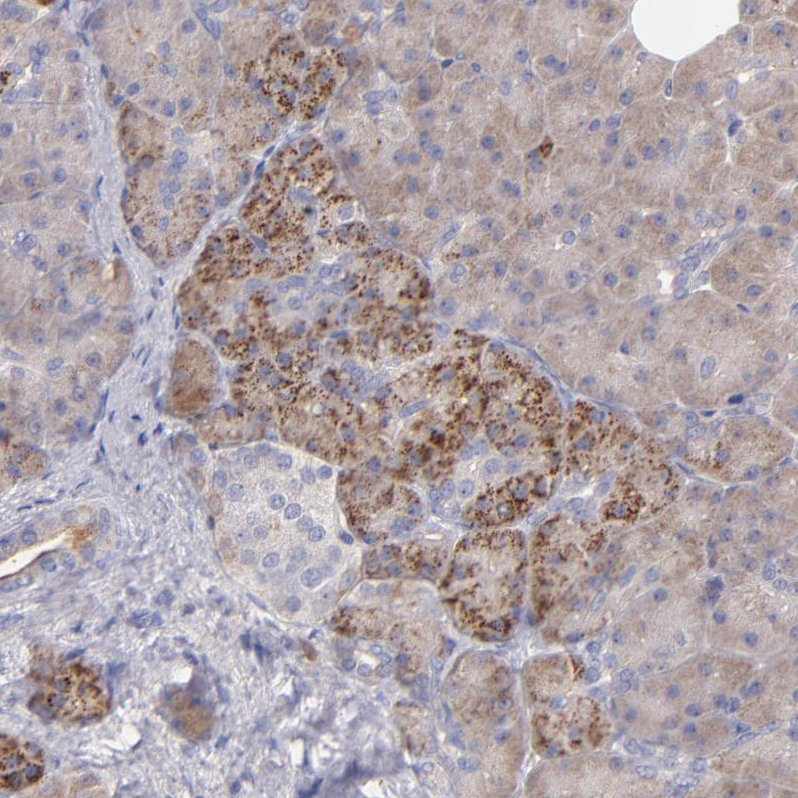

Immunohistochemical staining of human placenta shows moderate granular cytoplasmic positivity in trophoblastic cells.